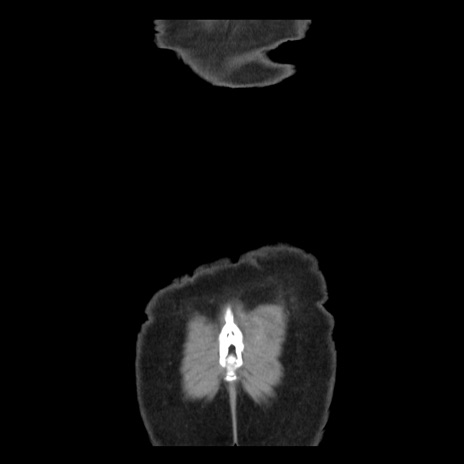

横断像

【症例】 50歳代女性

【主訴】 腹痛

【現病歴】前日生レバーを食べた。今朝に排便あり。 昼前に突然発症の腹痛を生じ、当院救急外来を受診した。

【既往歴】 子宮筋腫にてで子宮全摘後

【身体所見】 意識清明、腹部:平坦、軟、下腹部やや左を中心に圧痛・反跳痛あり、筋性防御あり

【データ】WBC 7800、CRP 0.07